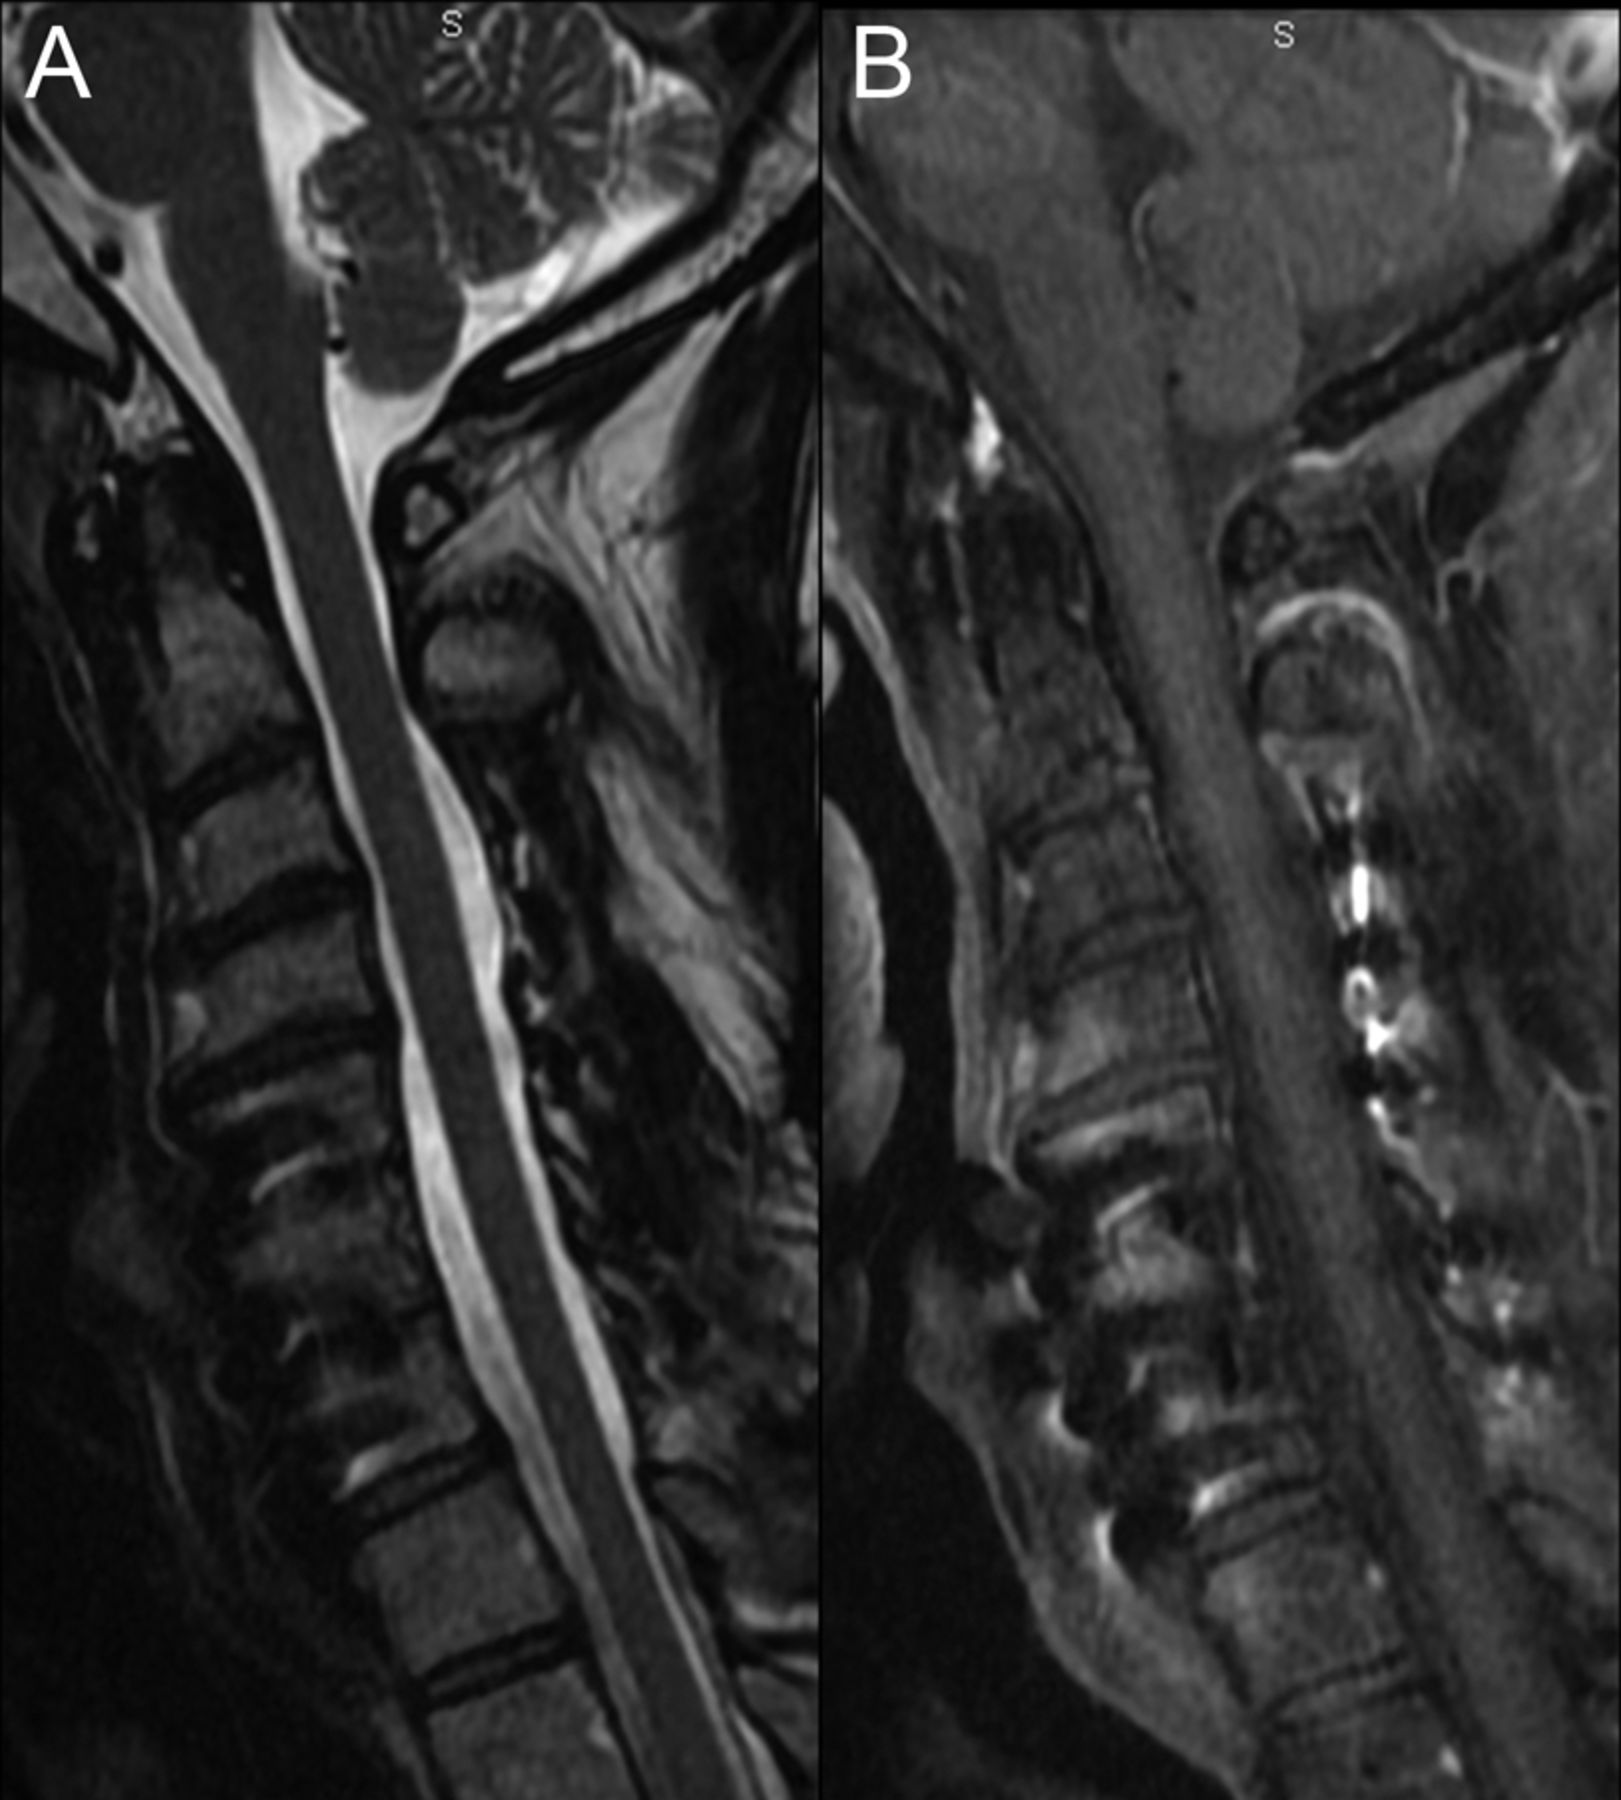

一个44岁的男人提供2周的进步对身体麻木,软弱,圆周烧灼感在他的躯干。脊柱MRI显示纵向广泛脊髓炎(图1)。MRI大脑和实验室调查除了脑脊液淋巴细胞是正常脑脊液细胞增多(9白细胞/毫米3)。CT显示肺门和纵隔淋巴结病,活检显示noncaseating肉芽肿结节病的暗示。作为病人有多个临床复发类固醇,他与英夫利昔单抗治疗输液(5毫克/公斤每4周),而且有完整的临床和放射分辨率后1年(图2)。脊髓炎呈现结节病的特点是非常罕见的,对英夫利昔单抗。1,2